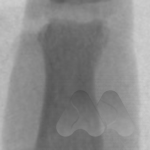

Carpal tunnel syndrome affects the median nerve that travels through a space that connects the forearm and hand at the front of the wrist. Pressure on the nerve, from many possible causes, can lead to a slowing of the electrical signals that supply sensation to the thumb, index and middle finger. It can lead to tingling and numbness in these fingers or the whole hand and can often be worse at night time.